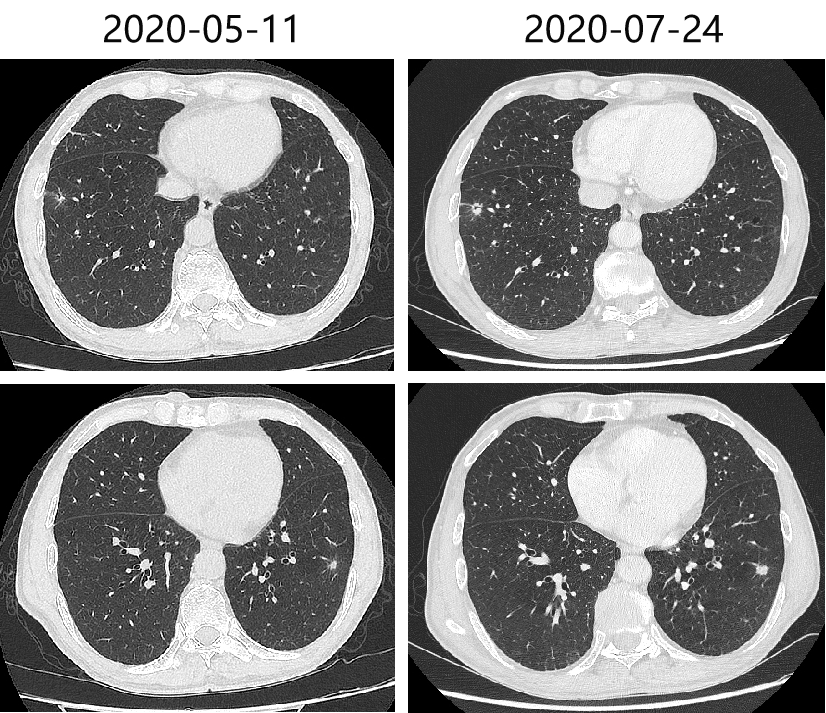

2019-11-11、2020-03-10、2020-05-11 复查CT评价SD。

头胸腹盆增强CT(2020-07-24)示:双肺多发结节,部分较前(2020-05-11)明显增大,考虑转移灶;肝左叶占位,考虑转移,较前(2020-05-19)增大;考虑病情进展。

肺:肺部多发结节,部分较前(2020-05-11)明显增大,考虑转移。考虑PD。

肝:肝左叶占位,考虑转移,较前(2020-05-11)增大;考虑PD。